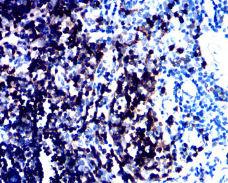

CD1a Mouse Monoclonal antibody[7C7F7]

IHC    1/200 - 1/1000